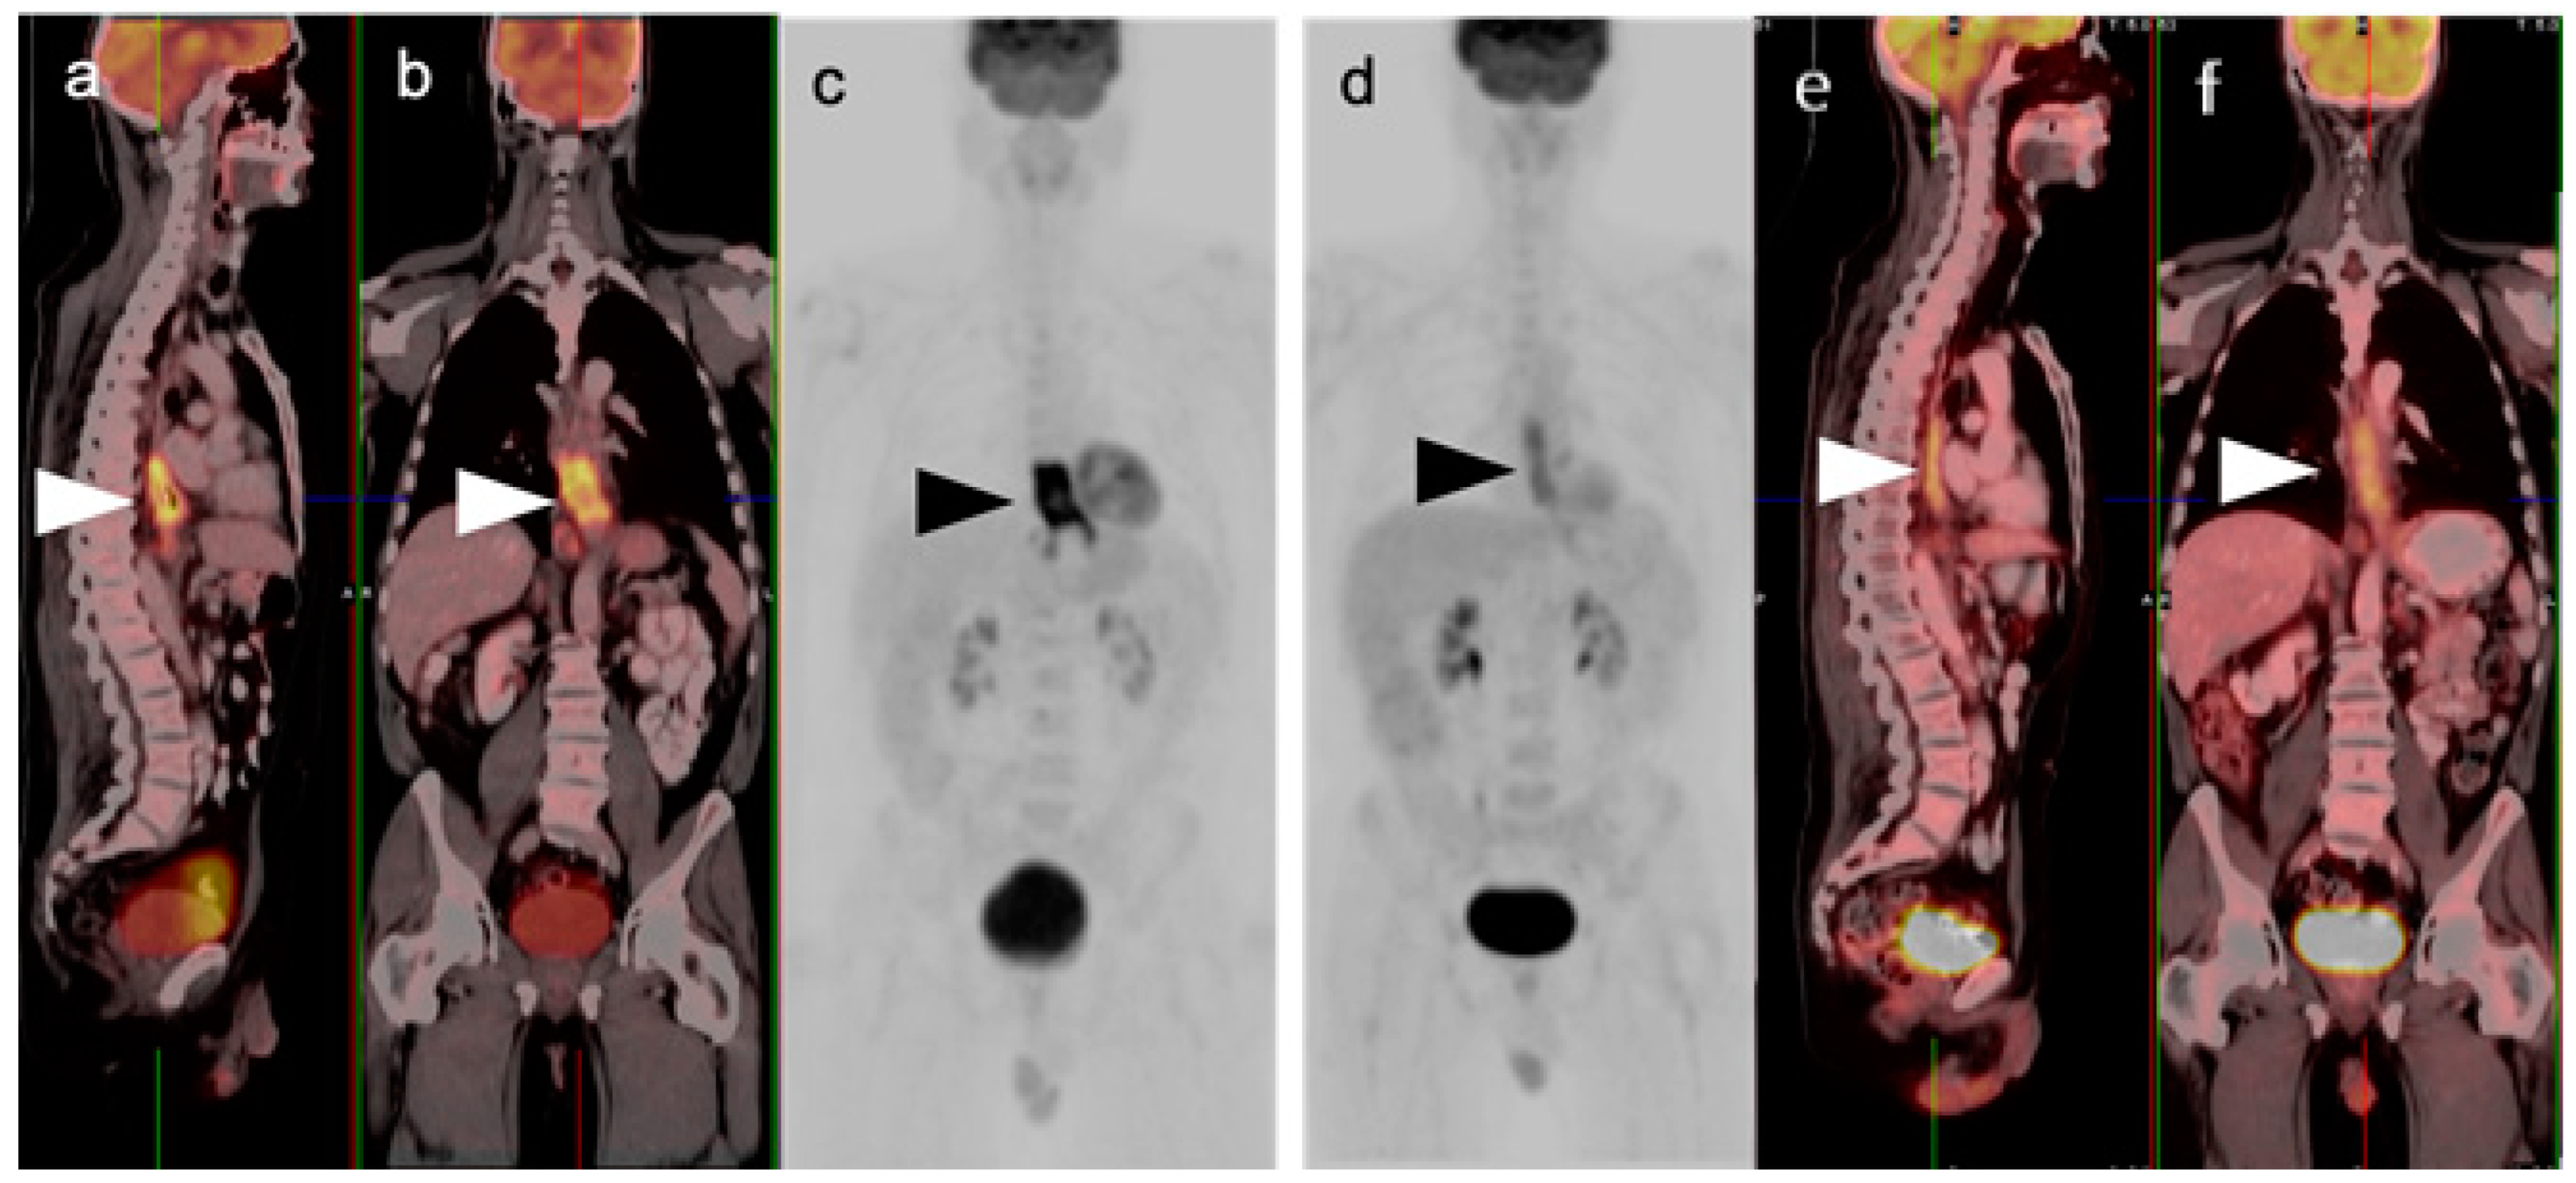

3. Gastrointestinal Stromal Tumor (GIST)